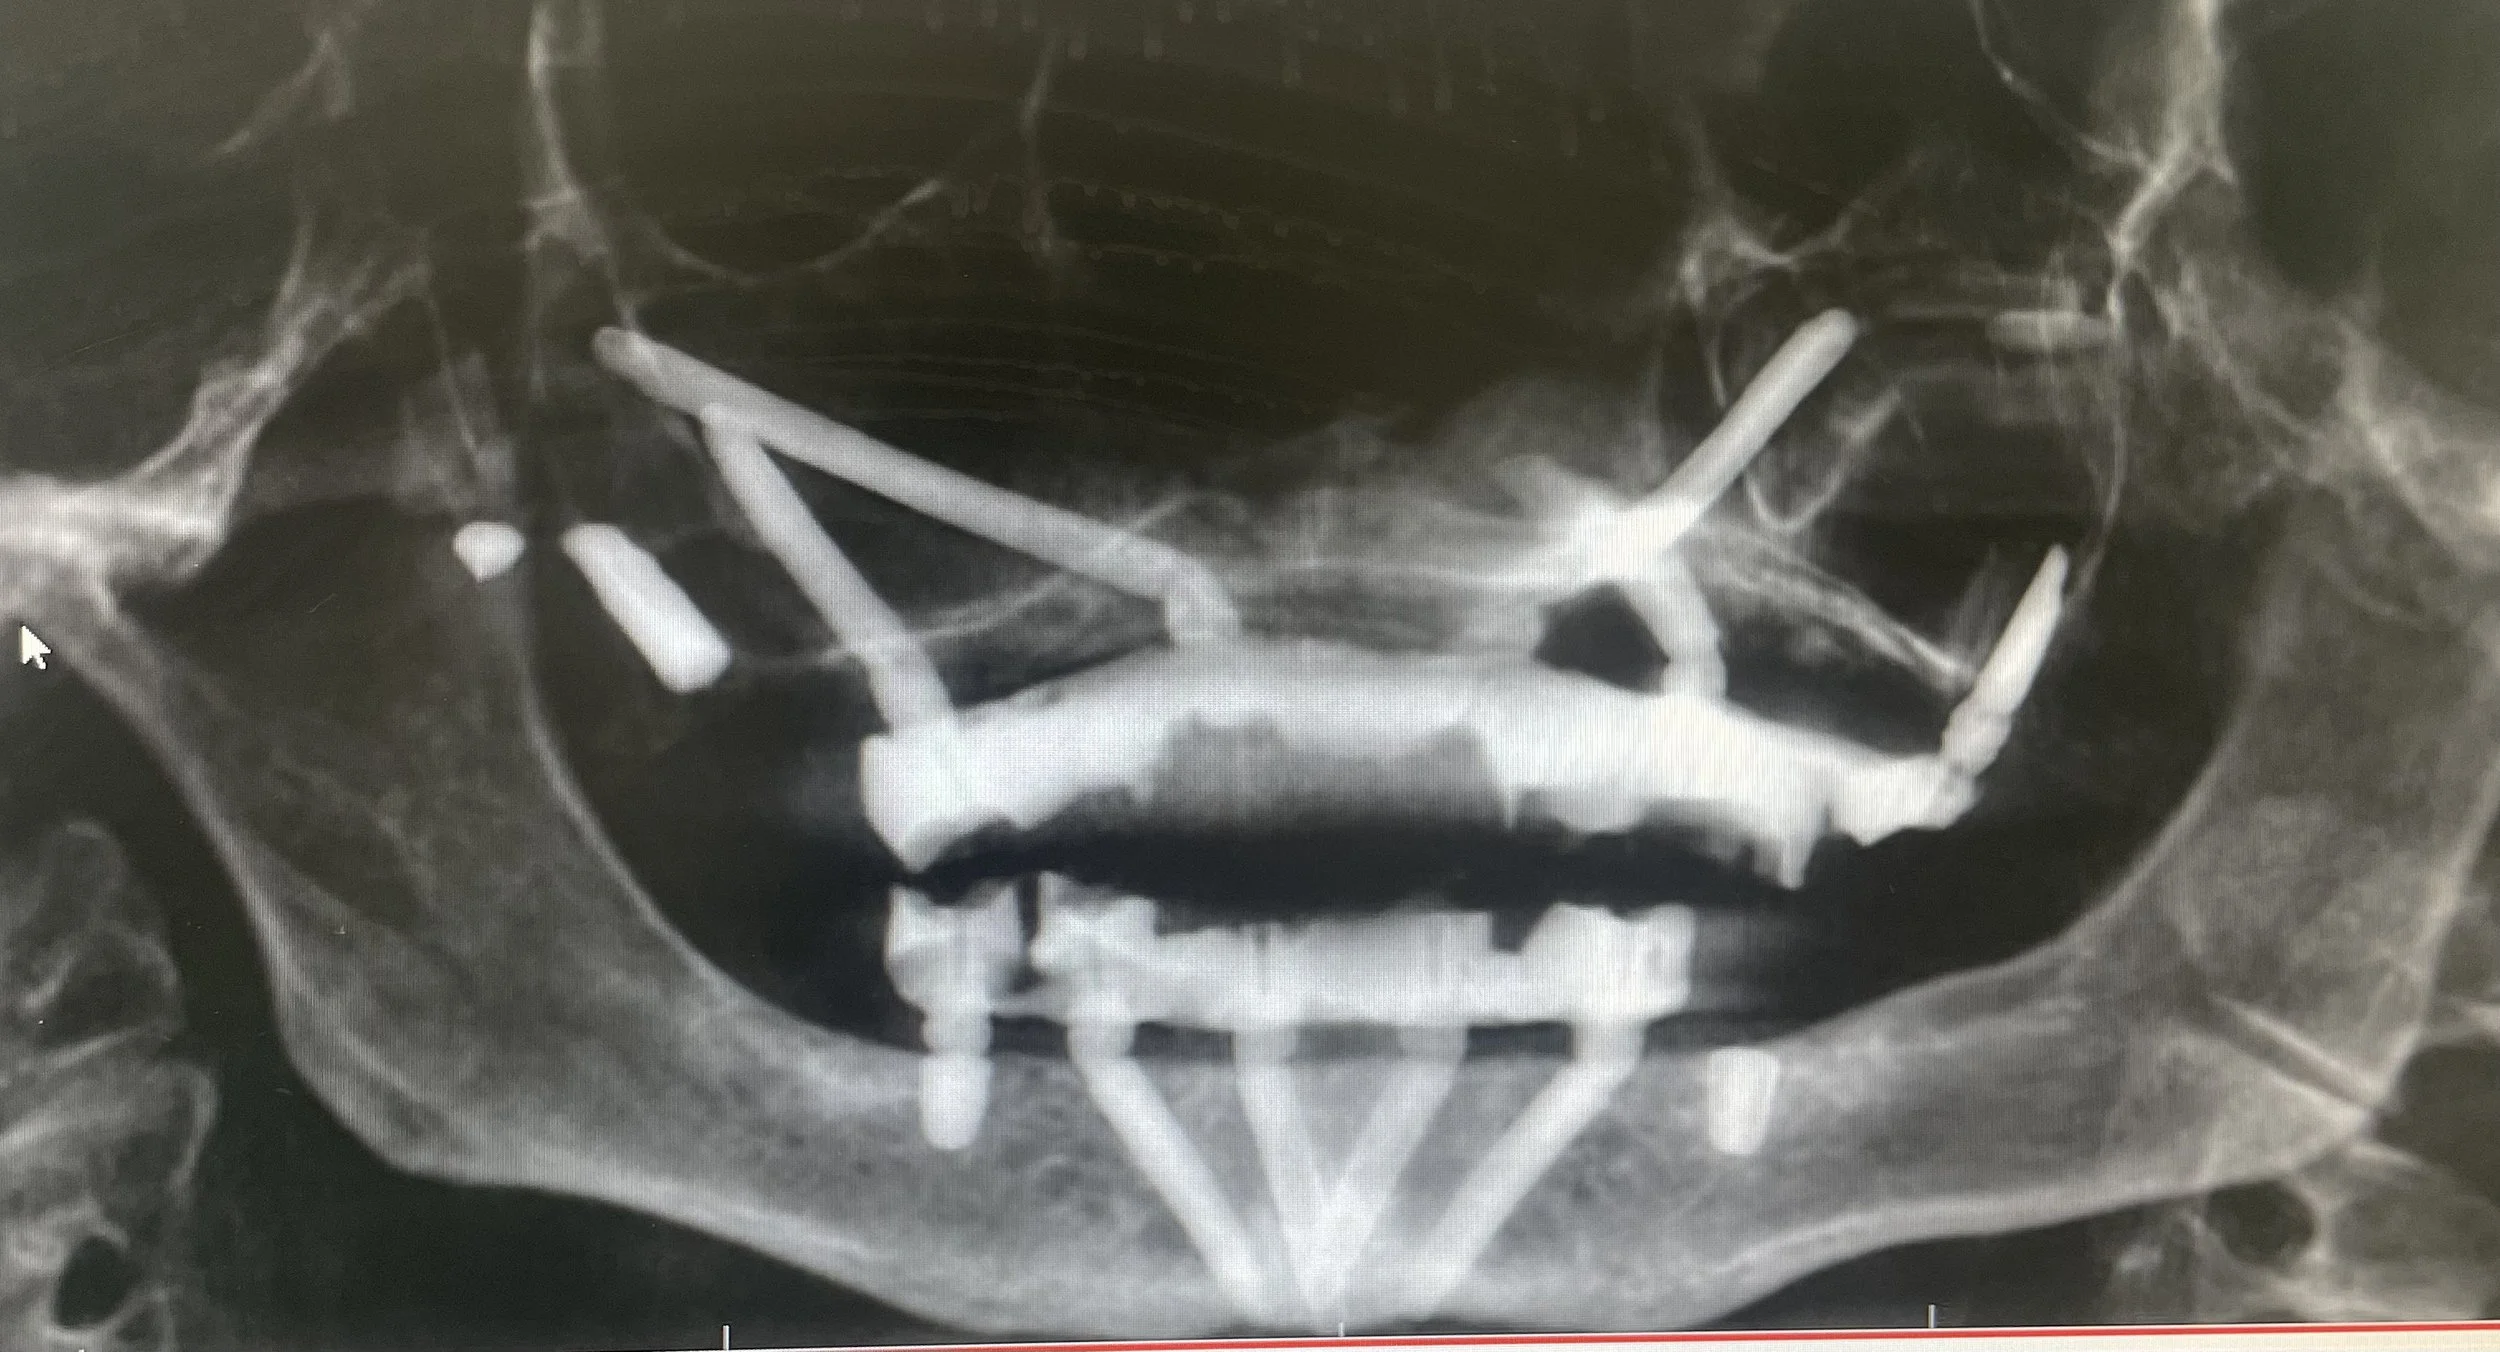

Dr. Damons Cases